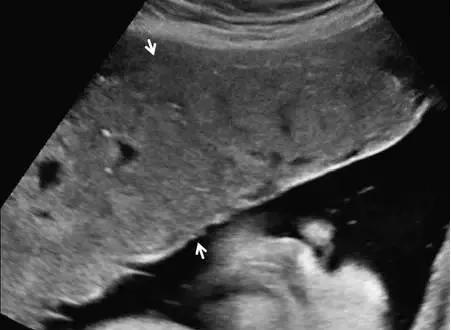

超声最早可在孕 6 周(经阴道超声)或孕 10 周(经腹部超声)显示出胎盘,表现为妊娠囊周围的薄层环状高回声。妊娠 12~13 周时,多普勒超声可显示绒毛血流。孕 14~15 周时,胎盘已充分发育,表现为显著的高回声。此时,也可看到由蜕膜、肌壁、子宫血管等组成的胎盘后复合体(图 1)。

中孕时,胎盘逐渐成熟变大,表现为更加均质的高回声(图 2),其内可有边界欠清的低回声区,为胎盘湖。晚孕时,多普勒超声可显示胎盘内的丰富血流。

图 1 孕 12 周时的正常胎盘矢状面,其后可见低回声的胎盘复合体(小箭头)

图 2 孕 24 周时的正常胎盘横切面,显示胎盘的回声、厚度及其后方的低回声肌壁(箭头)